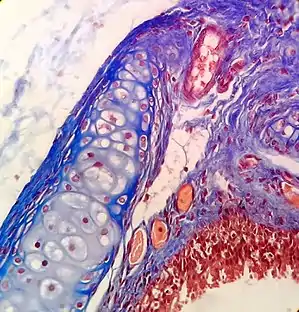

Staining

Biological tissue has little inherent contrast in either the light or electron microscope.[17] Staining is employed to give both contrast to the tissue as well as highlighting particular features of interest. When the stain is used to target a specific chemical component of the tissue (and not the general structure), the term histochemistry is used.[9]

Light microscopy

Hematoxylin and eosin (H&E stain) is one of the most commonly used stains in histology to show the general structure of the tissue.[9][20] Hematoxylin stains cell nuclei blue; eosin, an acidic dye, stains the cytoplasm and other tissues in different stains of pink.[9][12]

In contrast to H&E, which is used as a general stain, there are many techniques that more selectively stain cells, cellular components, and specific substances.[12] A commonly performed histochemical technique that targets a specific chemical is the Perls' Prussian blue reaction, used to demonstrate iron deposits[12] in diseases like hemochromatosis. The Nissl method for Nissl substance and Golgi's method (and related silver stains) are useful in identifying neurons are other examples of more specific stains.[12]